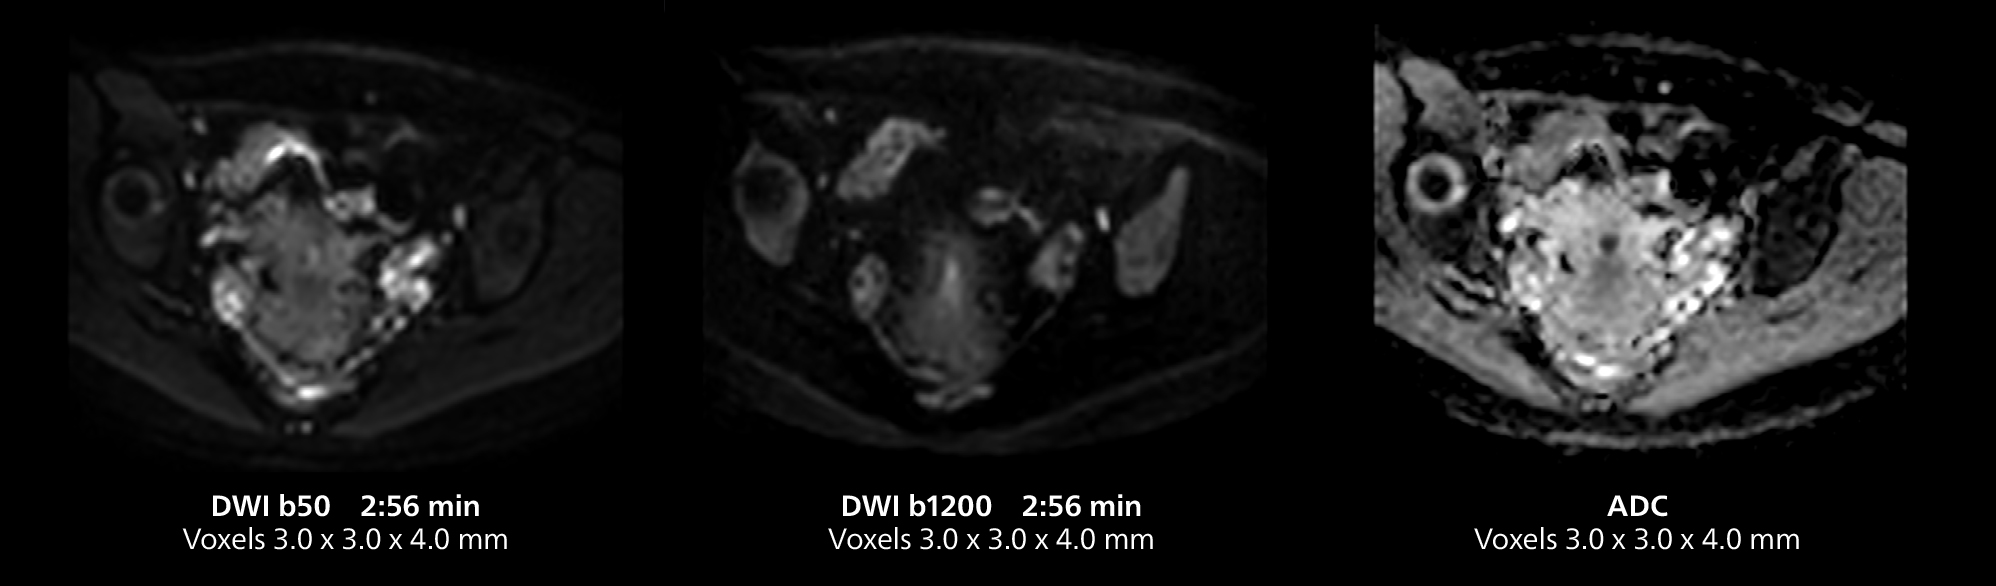

Female pelvis imaging

This MRI case illustrates good resolution and imaging quality obtained within reasonable scan times using the MR 5300 1.5T system with the anterior torso cardiac coil that allows use of a large field of view (FOV).